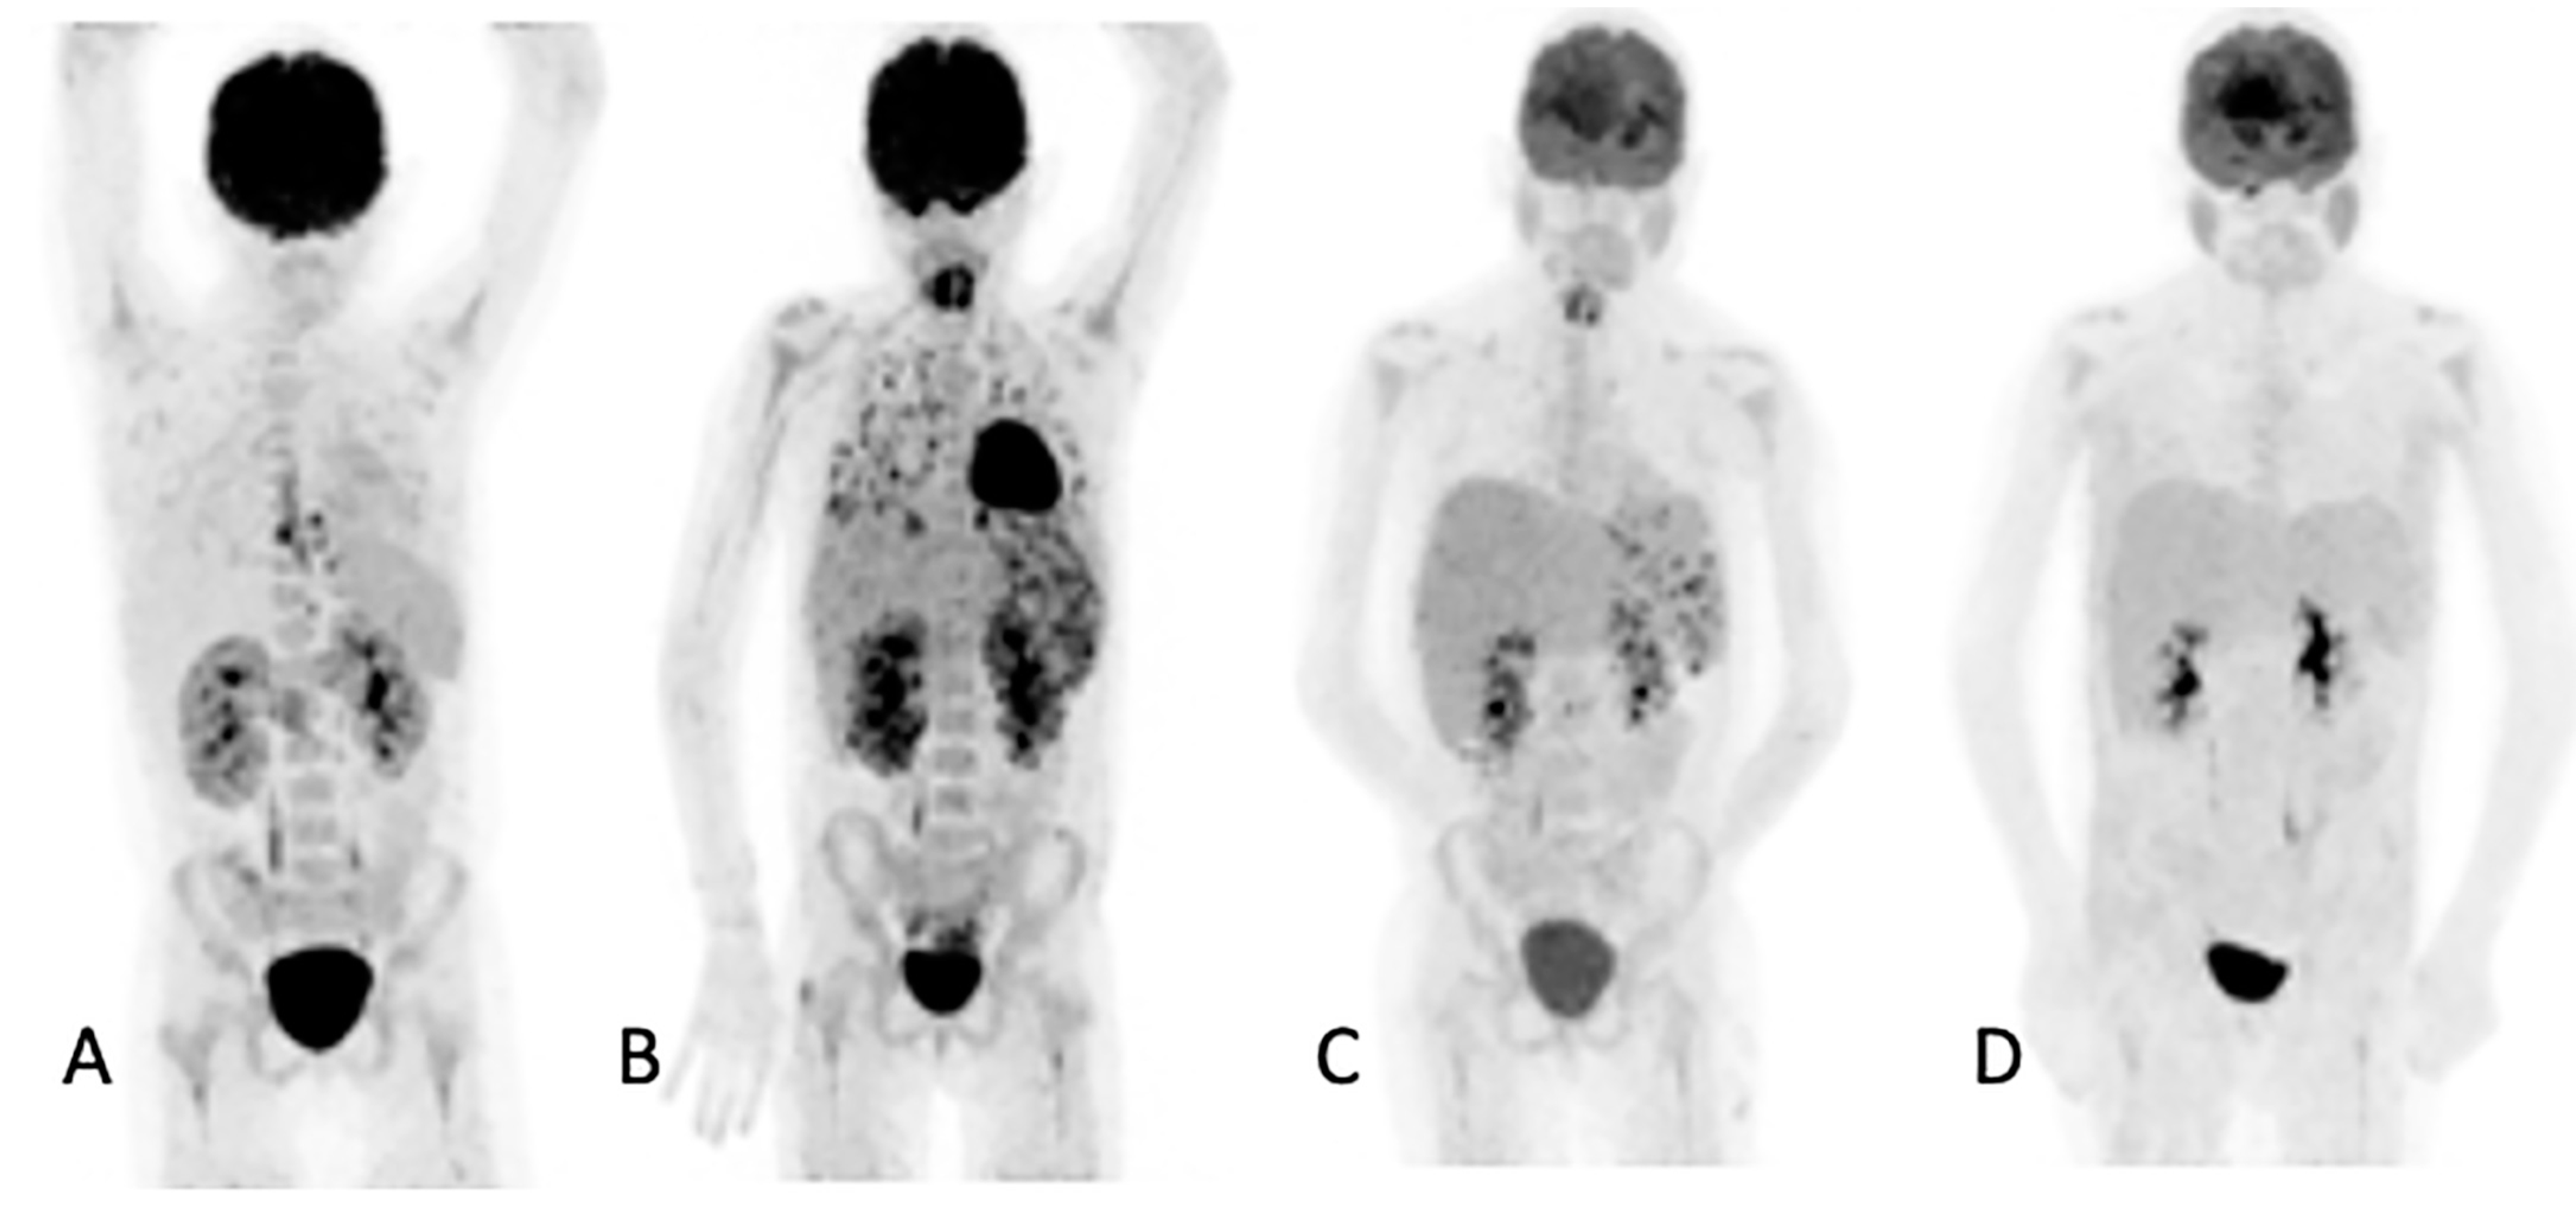

In the 32 patients that had repeated [18F]FDG PET/CT imaging to assess the responses, the follow-up helped the clinicians to decide to stop, continue or change antifungal therapy (Figure 3). [18F]FDG PET/CT detected previously unknown IFI lesions in five patients of the 18 that were referred for the staging of the infection, which led to therapy prolongation in four and a change in therapy in one. In the 10 patients with indications of unexplained fevers or increasing infective markers, [18F]FDG PET/CT was found to be useful in four patients, as it guided the biopsy that led to the diagnosis of the IFI (see Figure 4). In the seven patients that were being prepared for ASCT, [18F]FDG PET/CT was considered to add value for all. In four patients, the [18F]FDG PET/CT allowed clinicians to proceed with the procedure; in two others, further antifungal therapy was provided with follow-up with [18F]FDG PET/CT, and a biopsy was conducted in one of the patients before ASCT was performed. Finally, in the six patients where scans was performed to assess metabolic activity in residual anatomic lesions, [18F]FDG PET/CT was considered useful. There was a complete metabolic response in five patients, and in two patients, further antifungal treatment was instituted. Table 5 tabulates the patients for which [18F]FDG PET/CT was deemed to have added value. Figure 4 shows a female patient with acute myeloid leukemia while on antifungal therapy, where [18F]FDG PET/CT explained the increasing infective markers by demonstrating multiple IFI lesions outside the thorax.

Figure 3.

Ten-year-old female with acute myeloid lymphoma who developed a fever, on chemotherapy, with no response to antibiotics. An abdominal ultrasound demonstrated bilaterally enlarged kidneys. Initial [18F]FDG PET/CT MIP image (A) showed focal metabolic uptake in kidneys, spleen and esophagus. She was started on antifungal treatment, but the fever persisted, and a repeat study (B) showed the worsening of renal splenic lesions with no pulmonary lesions. The antifungal treatment was changed; the fever subsided, and the serum infective markers decreased. A repeat [18F]FDG PET/CT performed after 6 weeks (C) showed resolution of the pulmonary and most of the renal and splenic lesions. The treatment was continued for another month, and a follow-up [18F]FDG PET/CT (D) showed a complete metabolic response that helped the clinician to end the antifungal treatment.